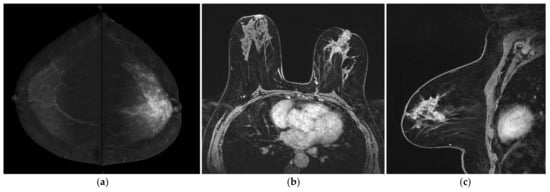

According to MRI-BI-RADS lexicon, the internal enhancement pattern of non-mass lesions includes homogeneous, heterogeneous, clumped and clustered rings [46]. These descriptors are hard to apply in CESM (Figure 5 and Figure 6).

Figure 5.

A 49-year-old women with large CLI of the left breast. Patient performs mammography because of a nipple retraction of the left breast. (a) CESM CC views show non-mass pathological enhancement on the left breast extending to the nipple. (b) Axial and (c) sagittal post-contrast T1-weighted fat saturation dynamic sequence (Vibrant) show large clustered ring regional non-mass enhancement consistent with pleomorphic CLI (T3 N2 M0, ER 90%, PgR 50%, Ki-67 35%, G3).